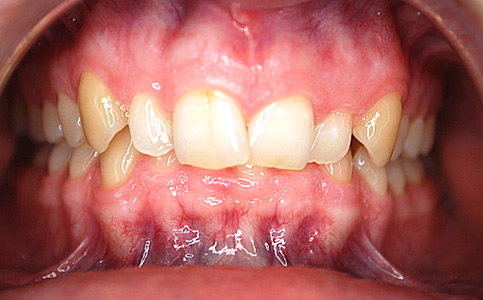

Kompleksowa metamorfoza naszego Pacjenta obejmowała leczenie ortodontyczne nakładkami invisalign oraz korektę zębów przednich BONDINGIEM- estetycznymi odbudowami kompozytowymi. Po zakończonym leczeniu Pacjent jest szczęśliwym posiadaczem pięknego prostego uśmiechu.

Zobacz efekty przeciągając suwak w prawo lub w lewo.